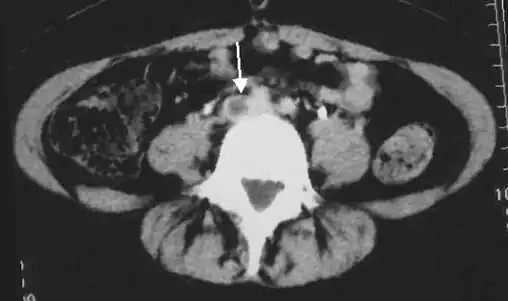

Thrombolysis is the injection of an enzyme into the veins to dissolve blood clots, and while this treatment has been proven effective against the life-threatening emergency clots of stroke and heart attacks, randomized controlled trials[139][140][141] have not established a net benefit in those with acute proximal DVT.[5][142] Drawbacks of catheter-directed thrombolysis (the preferred method of administering the clot-busting enzyme[5]) include a risk of bleeding, complexity,[l] and the cost of the procedure.[125] Although, while anticoagulation is the preferred treatment for DVT,[125] thrombolysis is a treatment option for those with the severe DVT form of phlegmasia cerula dorens (bottom left image) and in some younger patients with DVT affecting the iliac and common femoral veins.[12] Of note, a variety of contraindications to thrombolysis exist.[125] In 2020, NICE kept their 2012 recommendations that catheter-directed thrombolysis should be considered in those with iliofemoral DVT who have "symptoms lasting less than 14 days, good functional status, a life expectancy of 1 year or more, and a low risk of bleeding."[138]

A mechanical thrombectomy device can remove DVT clots, particularly in acute iliofemoral DVT (DVT of the major veins in the pelvis), but there is limited data on its efficacy. It is usually combined with thrombolysis, and sometimes temporary IVC filters are placed to protect against PE during the procedure.[143] Catheter-directed thrombolysis with thrombectomy[141] against iliofemoral DVT has been associated with a reduction in the severity of post-thrombotic syndrome at an estimated cost-effectiveness ratio of about $138,000[m] per gained QALY.[144][145] Phlegmasia cerulea dolens might be treated with catheter-directed thrombolysis and/or thrombectomy.[19][143]